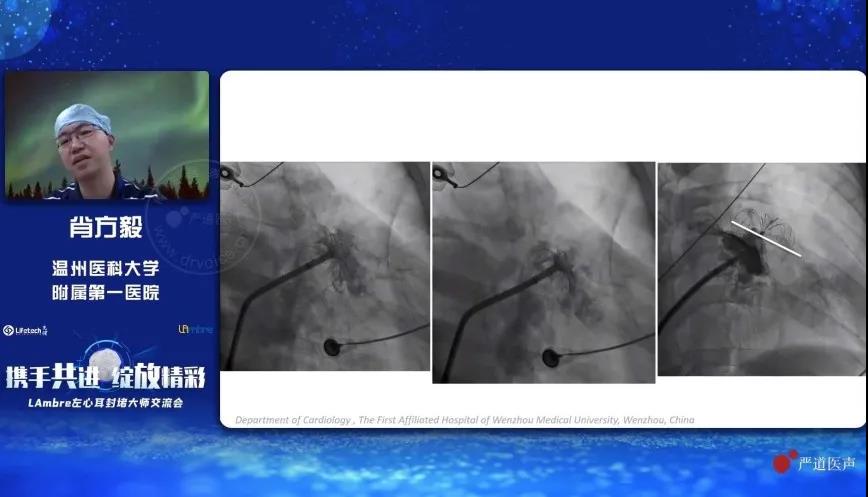

《LAmbre™封堵器渐进式操作技巧》

温州医科大学附属第一医院的肖方毅教授分享了使用“渐进式”方法操作LAmbre™左心耳封堵器系统进行手术封堵的技巧。肖教授对比了传统式与“渐进式”两种不同的左心耳封堵器输送方法,并通过详实的统计数据证明,使用“渐进式”方法可有效减少术中回收封堵器的次数,降低封堵器可能对左心耳带来的潜在损伤。此外,肖教授特别指出,虽然“渐进式”方法具有明显的优势,但仍需结合患者的实际情况进行综合考量。